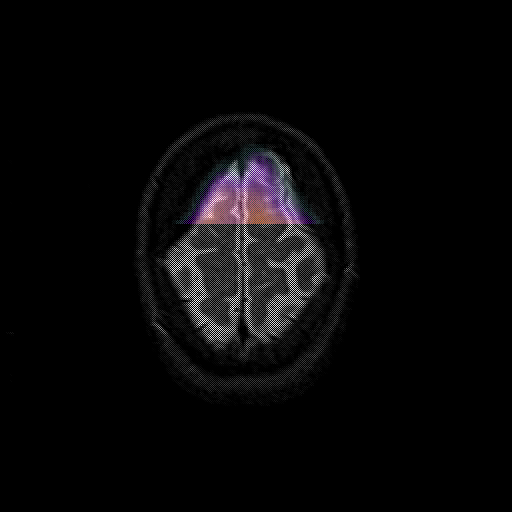

overlay 1: Slice 47

Slice 47

MRCBFCBF with

T1PDT2T1PDT2